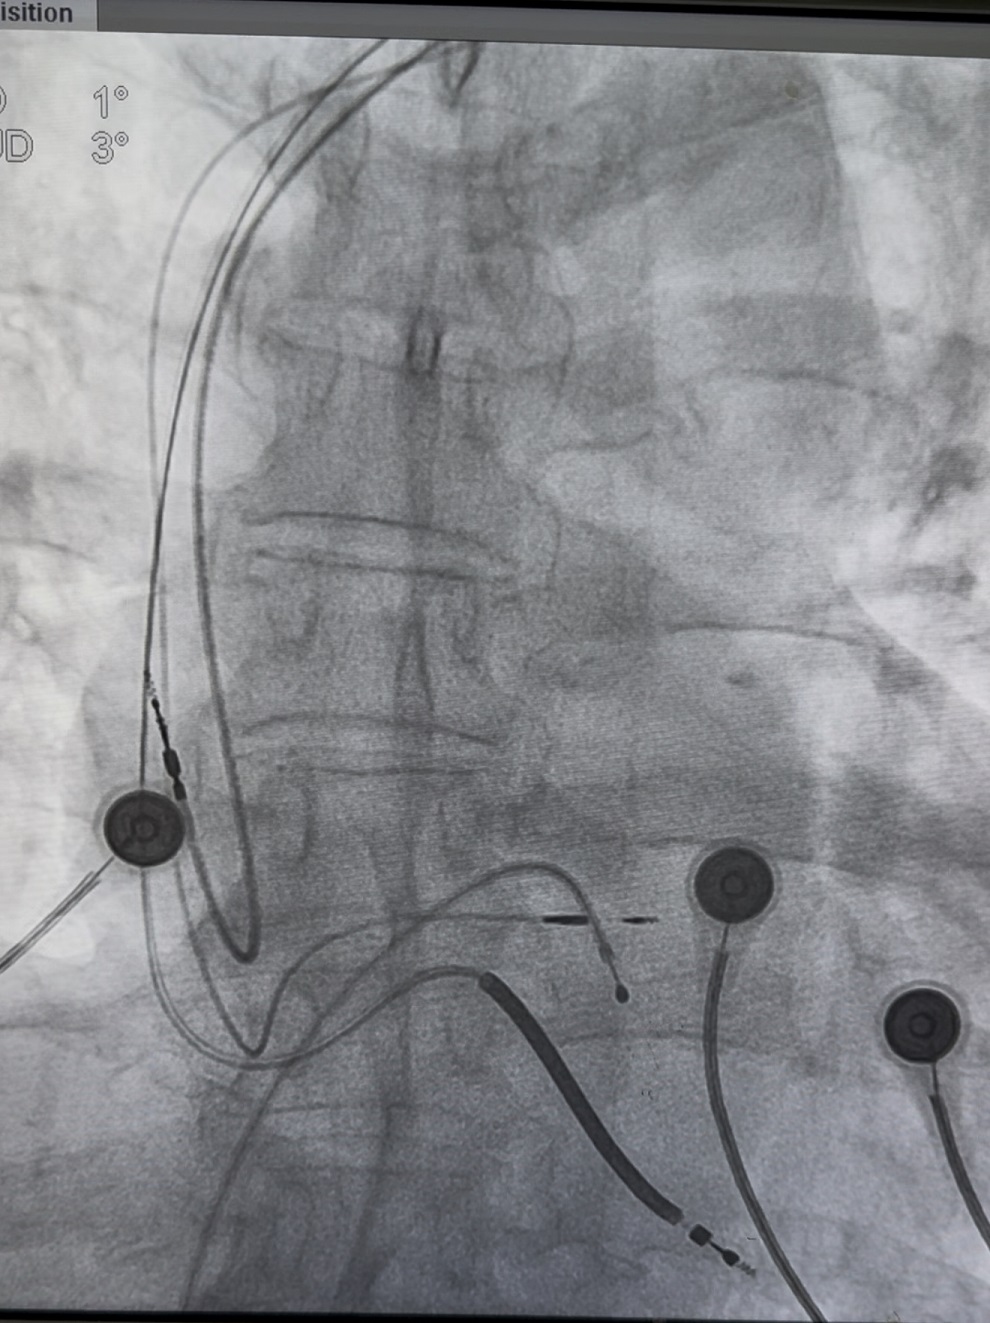

3.CRTD植入病人69岁男患,严重心功能不全,酒精性心肌病,EF=0.33,左心室直径75mm,真性完全性左束支阻滞。患者左右心室收缩不同步,心衰症状明显。CRTD植入指征明确。

介入手术由张晓君主任和张桐桐主治医师团队完成。术中置入右心室除颤电极、右房电极、心室除颤电极达右室心尖部,位置固定良好,测起搏阈值0.5V@0.42ms,阻抗为740ohm,测R 波感知>16mV;经导丝送入C315 HIS鞘管,在X线透视下将鞘管远端置于希氏束远端,沿鞘管送入3830螺旋电极,移动鞘管头端,寻找左束支区域,起搏 Tip 可见V1导联呈QS形,心电图底部有切迹,旋入心肌后起搏可见 V1导联演变为QR波,起搏 Ring 可见V1导联底部切迹,与旋入前Tip起搏形态相同,测试双极阈值0.7V@0.42ms,阻抗1020ohm,感知6.0mV;心房电极测阈值1.2V@0.42ms,P波感知4.0mV,阻抗560ohm。术后病人症状明显减轻,术中心电图为左束支起搏。